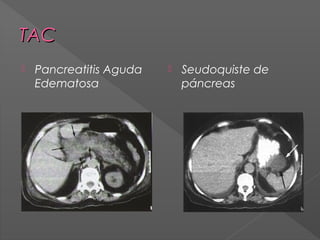

TAC

Pancreatitis Aguda

Edematosa

Seudoquiste de

páncreas